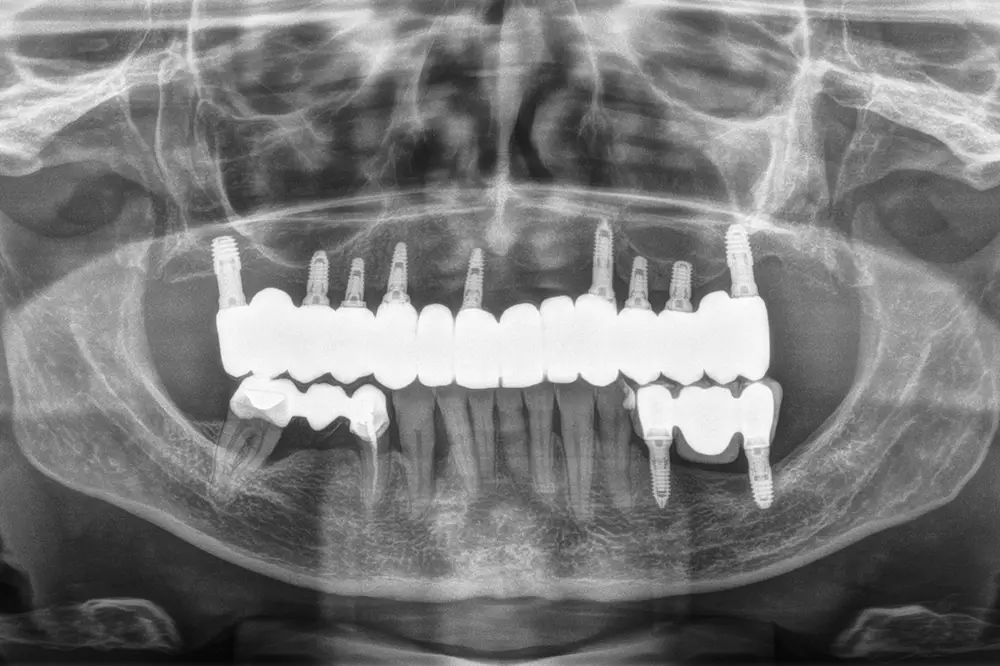

Para los sectores posteriores, se fabricaron estructuras mediante fresado CAD/CAM del mismo modo que la barra anteriormente descrita, con la diferencia de que sobre ellas se colocó un recubrimiento de cerámica (figs. 47-49). La paciente continúa en seguimiento, sin evidenciarse pérdidas óseas significativas en ninguno de los implantes estrechos y cortos que conforman la restauración de todo el maxilar superior tras tres años de carga de la prótesis definitiva (y hasta 4,5 de la carga de los implantes de la fase inicial de carga inmediata) (fig. 50).

Fig. 49. Radiografía final en el momento de colocación de la prótesis, dividida en los tres sectores.

Fig. 50. Imagen radiográfica de la paciente a los 3 años de la carga definitiva y 4,5 años tras la carga inicial de los implantes colocados inicialmente para la carga inmediata. En ella vemos la estabilidad del tratamiento en el tiempo de seguimiento ofrecido.